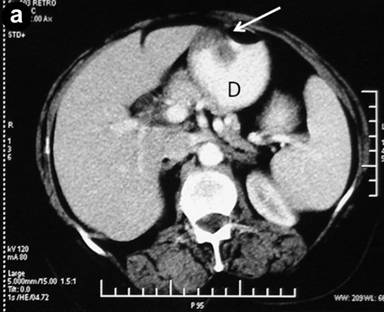

Abdominal ultrasonography showed a distended gallbladder without any calculi, prominent intrahepatic biliary radicals, a (10 mm) common bile duct dilated to the lower end with no calculi, prominent main pancreatic duct and a 2.8x1.9 cm hypoechoic mass near the distal end of the common bile duct. An abdominal computed tomography (CT) scan confirmed the dilatation of the common bile duct and the main pancreatic duct, and revealed an ill-defined hypodense mass 6.5x5.5 cm in size arising from the uncinate process of the pancreas (Figure 1). The mass involved the duodenum with an extension to the duodenojejunal flexure. The proximal duodenum was found to be dilated. The CT scan suggested the diagnosis of a pancreatic mass with duodenal infiltration. Upper gastrointestinal endoscopy was performed showing esophagitis and extraneous compression in the duodenal bulb. A side view endoscopy was performed and showed a long pedicle-like structure extending from the duodenal bulb into the distal duodenum along the medial wall of the second part of the duodenum (Figure 2). The distal end of this structure, the ampulla and the distal duodenal lumen could not be visualized. An attempt was made to pull the distal end of the structure using biopsy forceps but without success. Besides these findings, no ulcers, strictures or growths were found in the duodenum. In view of the endoscopic findings, the CT scan was again reviewed. The mass initially described as originating from the uncinate process was suspected to be intraluminal within the distal duodenum with a smooth outline at the distal end. However, this mass could not be defined as separate from the pancreas. In addition, a characteristic sign of “duodenal wall invagination” was observed in the dilated first part of the duodenum (Figure 3). Barium meal examination of the upper digestive tract showed a well defined smooth lobular filling defect in the dilated first part of the duodenum (Figure 4). Given the above findings, a duodenal polypoid mass of unknown nature was suspected. A side view endoscopy was repeated and endoscopic ultrasonography (EUS) was also performed. During this examination, a large polypoid mass with normal overlying mucosa was seen in the proximal duodenum (Figure 5a). The ampulla was seen as separate from the polyp and was found to be normal as was the visualized distal duodenum (Figure 5b). Endoscopic ultrasonography revealed a homogenous echogenic mass occupying the submucosa in the duodenal bulb with a normal pancreas which was not involved by the mass (Figure 5c). A biopsy taken from the polyp showed non-specific changes in the mucosa.

Figure 3. CT scan showing the dilated first part of the duodenum (D) along with the thickening and characteristic invagination of the anterior duodenal wall (arrows: invagination sign). |

They are usually asymptomatic and are discovered incidentally during endoscopy. Symptomatic cases most commonly present with gastrointestinal bleeding and obstruction [3]. Bleeding is often chronic and may be manifested as chronic anemia. Obstructive symptoms usually occur when they are larger than 2 cm [10]. Brunner’s gland adenoma may present with gastric outlet obstruction [11], duodenal obstruction, as in our case, or occasionally with the intussusception of the duodenal wall [12, 13, 14, 15]. The present case had chronic intermittent duodenal obstruction at the duodenojejunal flexure due to the intermittent prolapse of the polyp. This was evidenced by the presence of a dilated duodenum and the symptoms of gastroesophageal reflux. This obstruction was related to the large size of the polyp and, probably, also to duodenal intussusception. Our patient was having recurrent episodes of duodenal intussusception which were present at the time of the initial endoscopy as well as during the CT scan, as evidenced by the invagination of the duodenal wall (Figure 3). However, it was in the early stage and had already been reduced at the time of surgery.